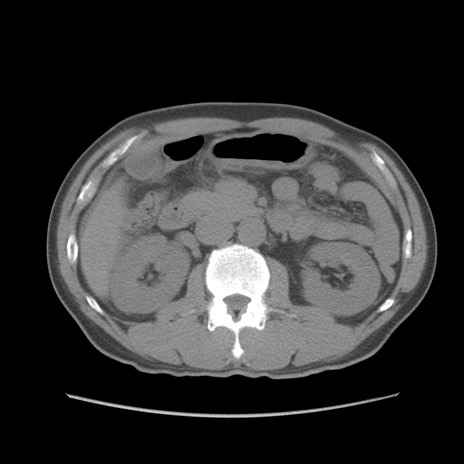

症例56 CT(横断像)

脂肪ウインドウ